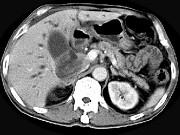

问题 男,58岁,患者右季肋区疼痛,皮肤黄染,可触及肿大胆囊,B超提示胆囊颈部肿块影,CT所见如图,最可能的诊断是()

选项 A.胆囊息肉 B.胆囊癌 C.胆囊黄色肉芽肿 D.慢性胆囊炎 E.胆囊腺肌增生症

答案 B